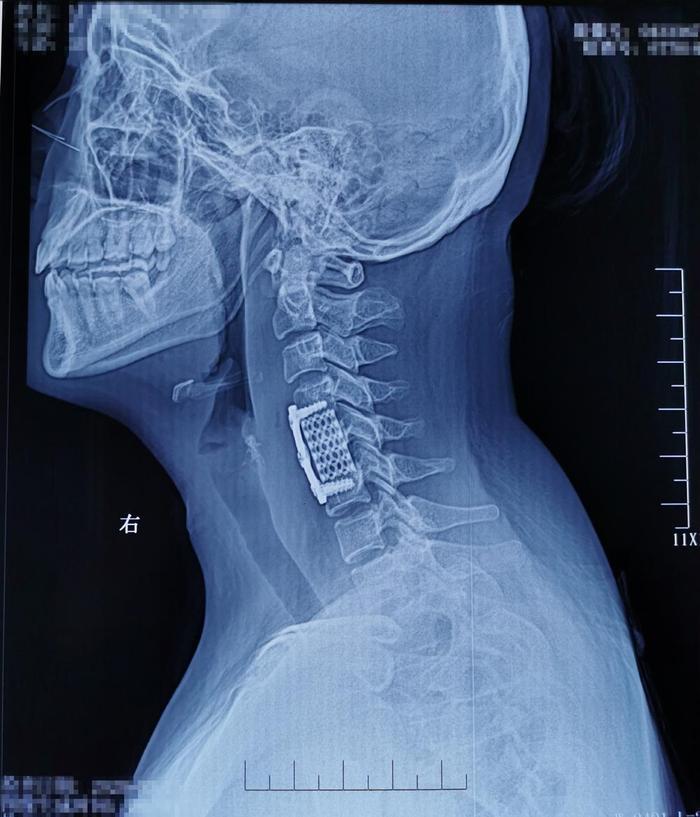

术后影像学资料: